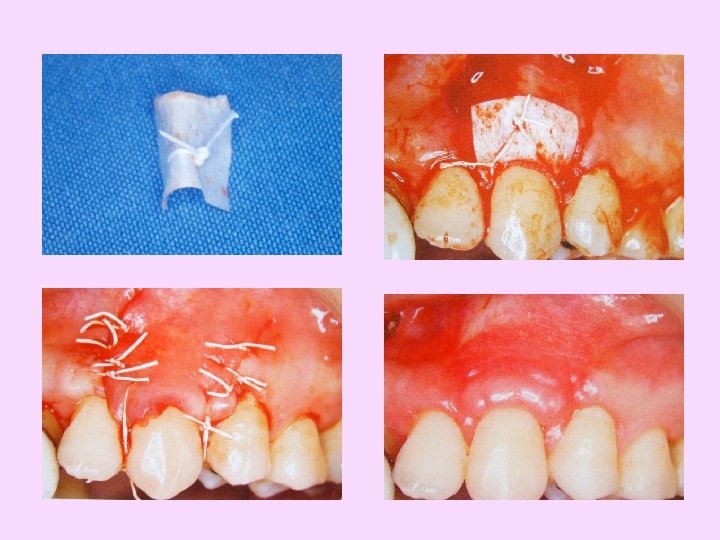

Sutures in place

Mattress suture

Membrane removal